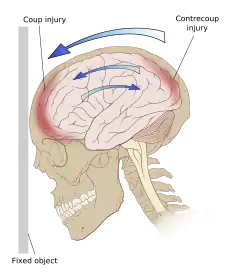

Even in the absence of an impact, significant acceleration or deceleration of the head can cause TBI; however in most cases, a combination of impact and acceleration is probably to blame.[66] Forces involving the head striking or being struck by something, termed contact or impact loading, are the cause of most focal injuries, and movement of the brain within the skull, termed noncontact or inertial loading, usually causes diffuse injuries.[67] The violent shaking of an infant that causes shaken baby syndrome commonly manifests as diffuse injury.[68] In impact loading, the force sends shock waves through the skull and brain, resulting in tissue damage.[66] Shock waves caused by penetrating injuries can also destroy tissue along the path of a projectile, compounding the damage caused by the missile itself.[32]

Damage may occur directly under the site of impact, or it may occur on the side opposite the impact (coup and contrecoup injury, respectively).[65] When a moving object impacts the stationary head, coup injuries are typical,[69] while contrecoup injuries are usually produced when the moving head strikes a stationary object.[70]